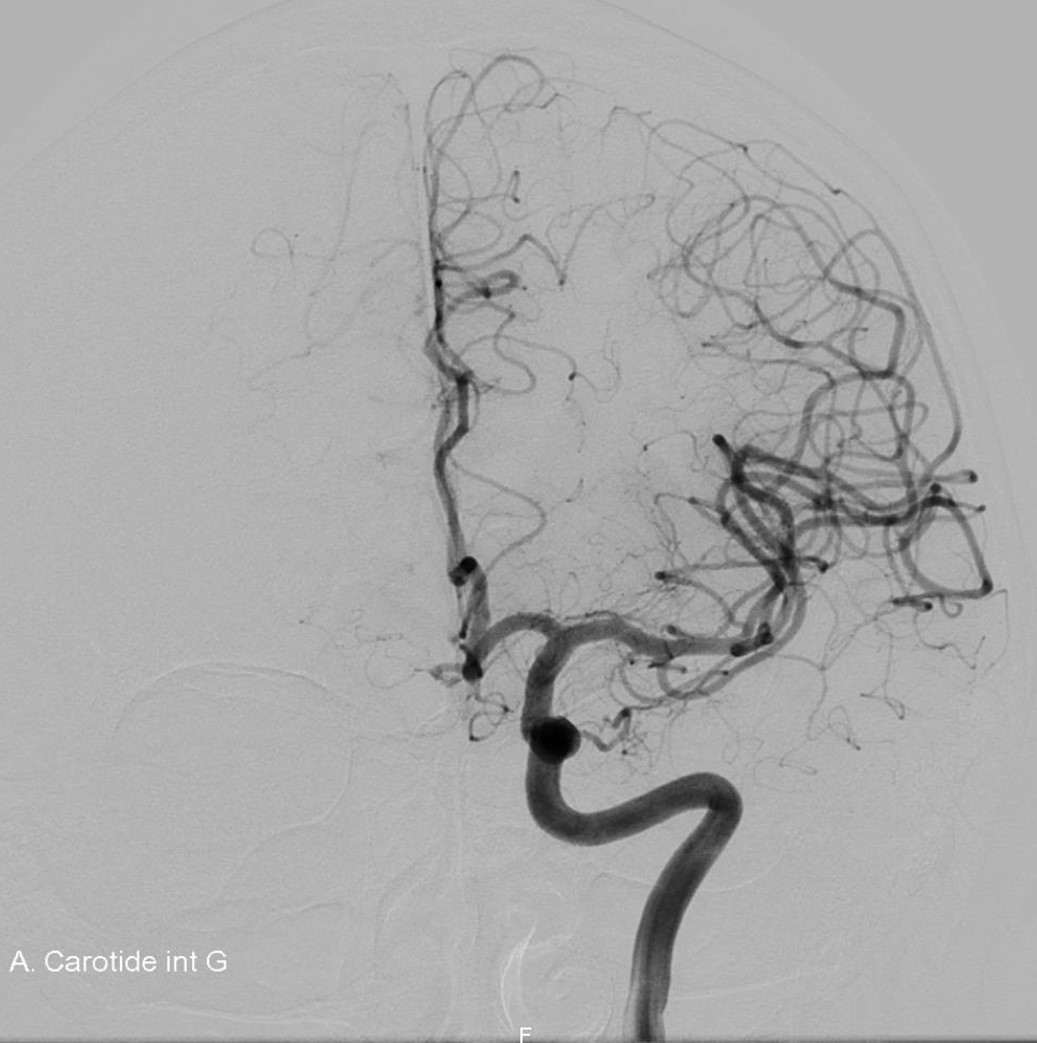

L’artériographie cérébrale, ou angiographie cérébrale, est une technique d’imagerie médicale diagnostique invasive qui permet de visualiser les vaisseaux sanguins du cerveau. Elle consiste à injecter un produit de contraste iodé directement dans les artères, via un cathéter (petit tuyau), ce qui rend les vaisseaux visibles par les systèmes d’imagerie à rayons X. Cette procédure est réalisée par un neuroradiologue interventionnel et permet d’obtenir des images très détaillées du réseau vasculaire cérébral.

L’artériographie cérébrale est utilisée pour diagnostiquer des pathologies vasculaires, tels que les anévrismes intracrâniens, les malformations ou fistules artério-veineuses, les vascularites et les sténoses artérielles. Il s’agit d’un acte interventionnel à visée diagnostique. L’extrême précision des images permet aux médecins de comprendre en détail et en 3D l’état vasculaire du patient et de décider des meilleures options de traitement.

Le médecin réalise d’abord une anesthésie locale puis réalise une piqûre au niveau du pli de l’aine afin d’insérer un cathéter (tuyau) dans l’artère fémorale. Sous guidage radiographique (rayons X), le cathéter est avancé jusqu’aux artères du cou qui alimentent le cerveau. Un produit de contraste iodé est ensuite injecté pour rendre les artères visibles sur les images radiographiques. Cette procédure prend entre 30 min. et 1 heure en fonction du nombre d’axes artériels à explorer, et le patient est conscient tout au long de l’examen. Dans de rares cas, une anesthésie générale peut être proposée.

L’artériographie cérébrale est la méthode la plus précise et l’examen de référence pour diagnostiquer les pathologies des vaisseaux sanguins du cerveau. Elle permet un diagnostic détaillé des affections vasculaires cérébrales, bien plus fin que d’autres techniques d’imagerie comme l’IRM ou le scanner. Grâce à sa haute résolution spatiale, elle est particulièrement efficace pour guider les traitements, comme l’embolisation d’un anévrisme.